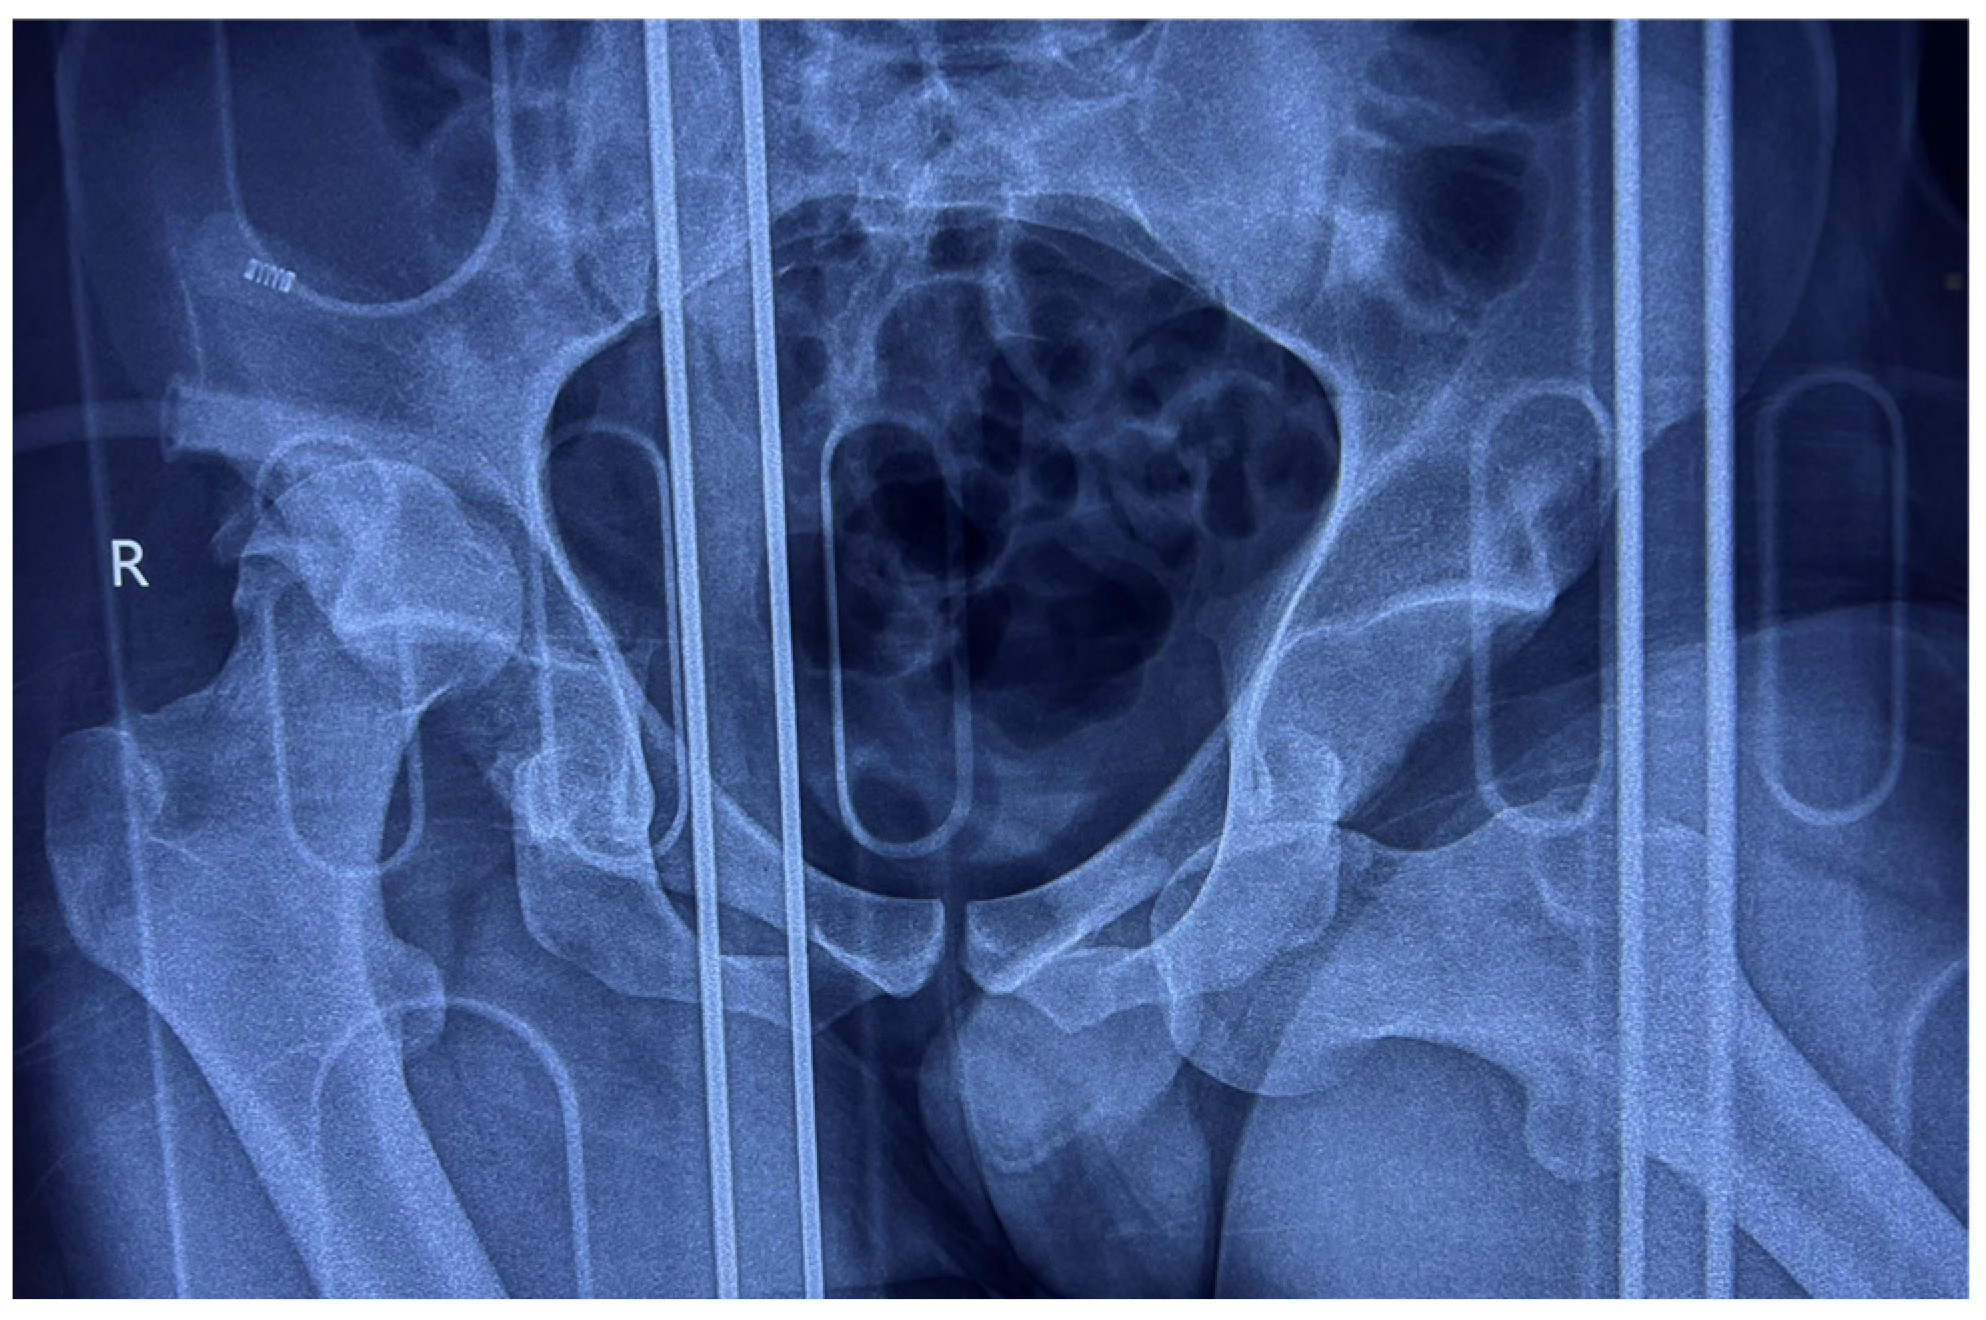

Anteroposterior (AP) pelvic radiographs immediately confirmed the presence of a bilateral asymmetric hip dislocation (Figure 1). The right femoral head was displaced posteriorly beyond the acetabular rim, with an associated acetabular posterior wall fracture, while the left femoral head was displaced anteroinferiorly into the obturator foramen, indicating an obturator-type anterior dislocation.

Figure 1. AP radiograph of the pelvis showing bilateral asymmetric hip dislocation with right femoral head displaced posteriorly beyond the acetabular rim, with an associated acetabular posterior wall fracture, while the left femoral head is displaced anteroinferiorly into the obturator foramen.